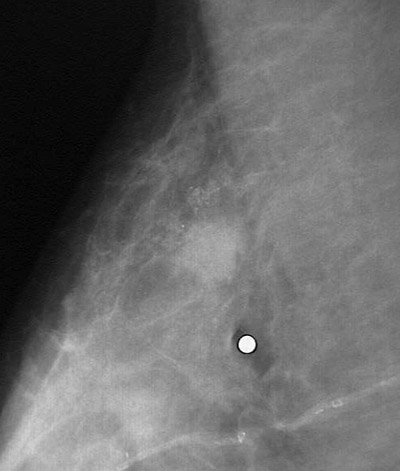

| A higher magnification of the previous mammogram demonstrates tiny peripheral calcifications marking a lesion consistent with a neoplasm in the upper portion above and just to the left of the white dot marking the point the patient felt some pain on palpation. On biopsy, this was an infiltrating ductal carcinoma. |